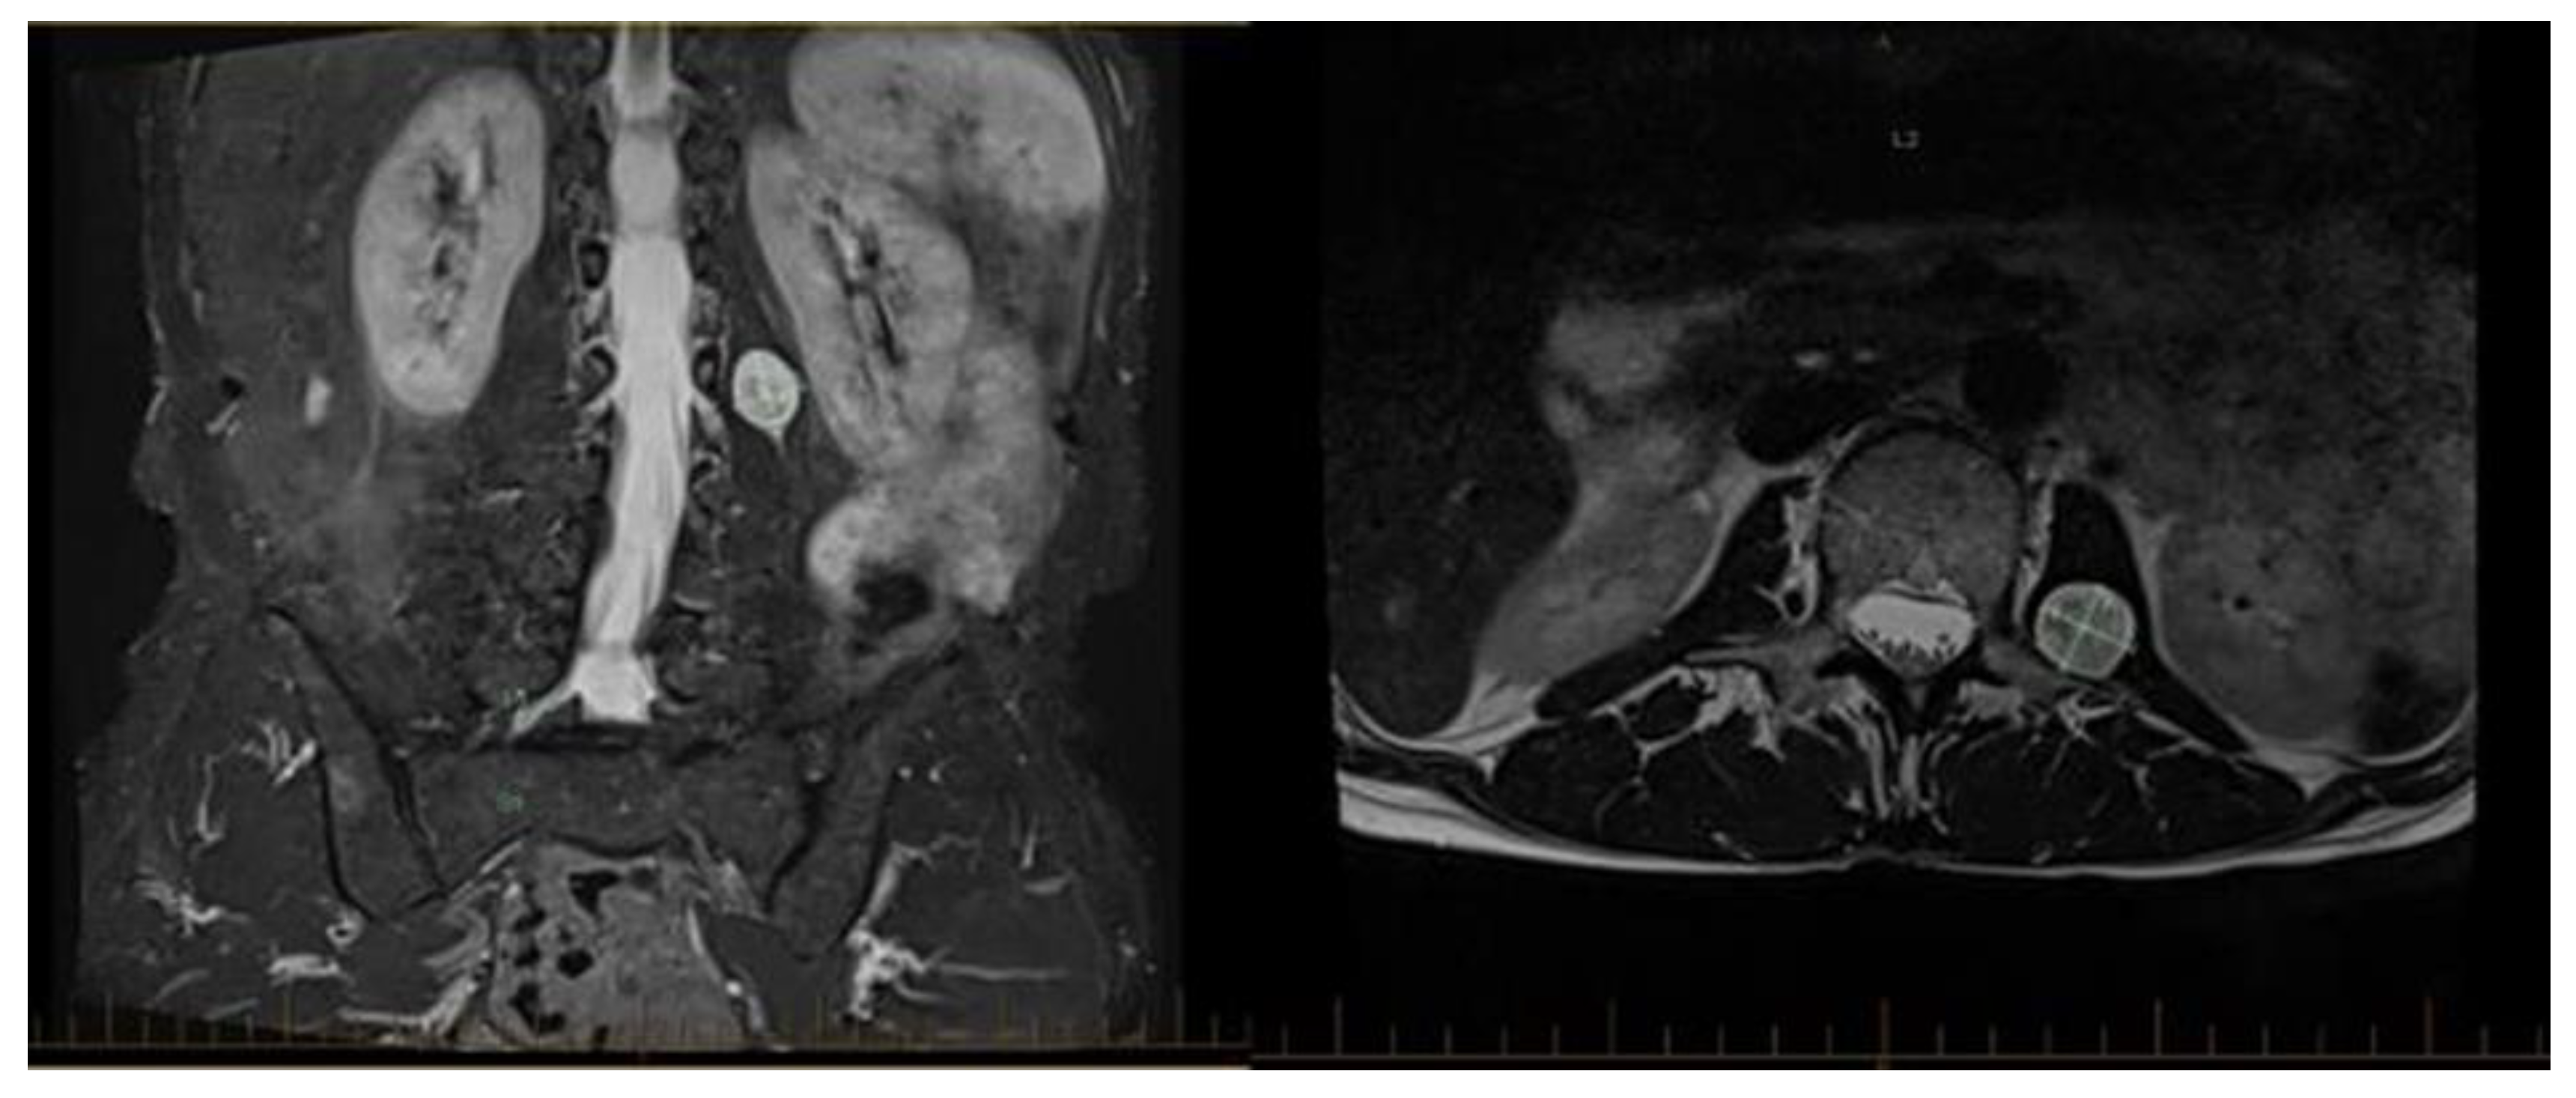

- Soliman, Y.; Feibus, A.H.; Baum, N. 3D printing and its urologic applications. Rev. Urol. 2015, 17, 20. [Google Scholar]

- Bernhard, J.-C.; Isotani, S.; Matsugasumi, T.; Duddalwar, V.; Hung, A.J.; Suer, E.; Baco, E.; Satkunasivam, R.; Djaladat, H.; Metcalfe, C.; et al. Personalized 3D printed model of kidney and tumor anatomy: A useful tool for patient education. World J. Urol. 2016, 34, 337–345. [Google Scholar] [CrossRef]